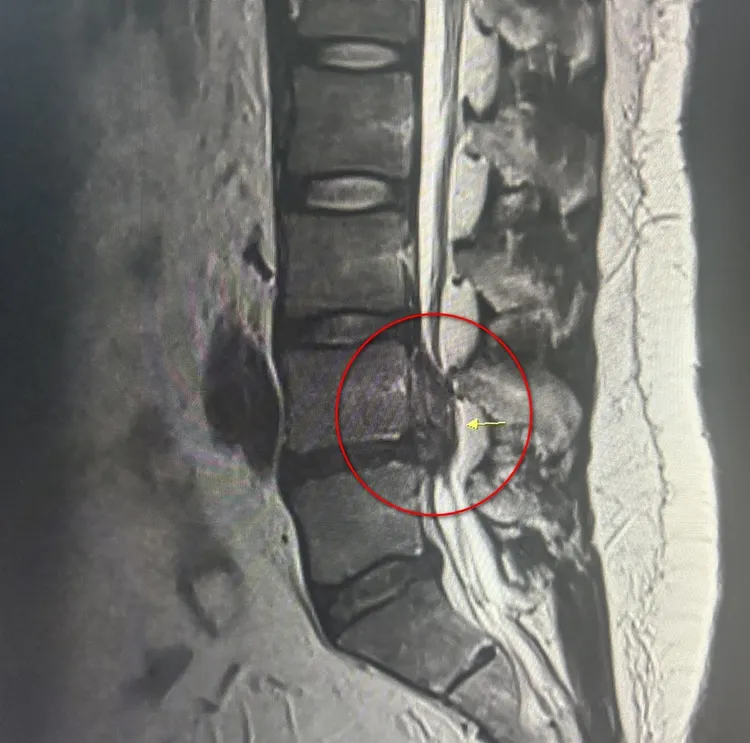

魏先生的第四、五節約有4公分大的椎間盤突出,嚴重壓迫神經。台北慈濟醫院提供